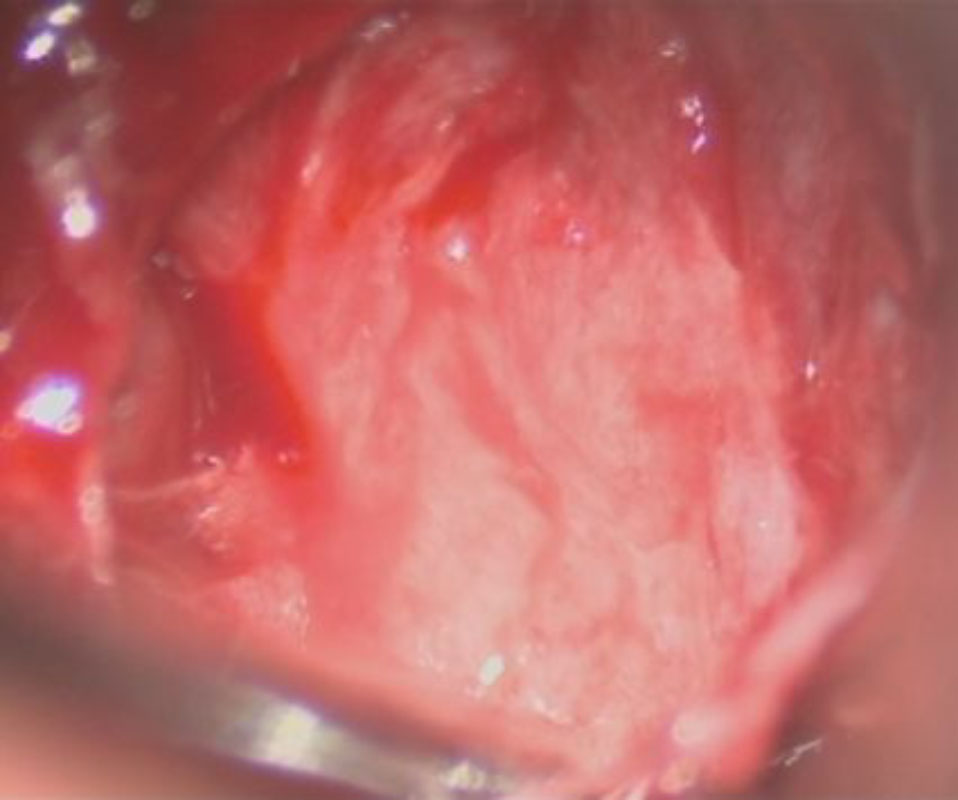

No.’25_74 摘出 後